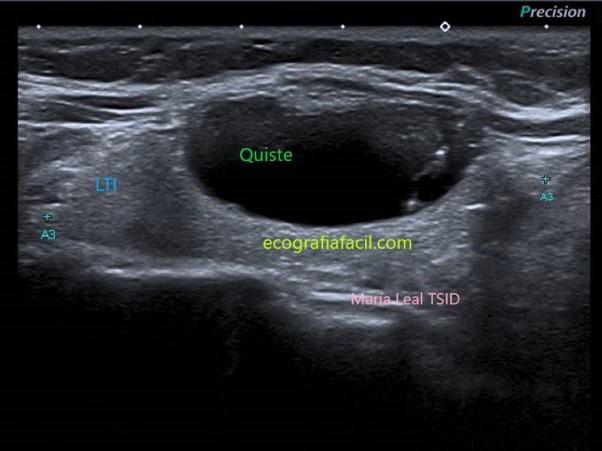

QUISTE:

Quiste

Los artefactos en “cola de cometa” son focos ecogénicos con forma en “V”. Se asocian con contenido coloide y son muy indicativos de benignidad cuando se encuentran dentro de componentes quísticos en los nódulos tiroideos.

ANECOICO: